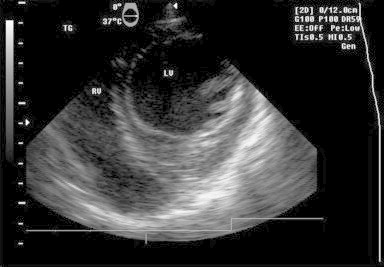

A 37-year-old man living in rural area, presented with history of non-specific chest pain for three months. His physical examination was normal but the chest radiograph displayed a well-defined smooth bulge over left cardiac border and positive hydatid serology (ELISA). The electrocardiogram (ECG) showed non-specific ST–T changes. Transthoracic echo (TTE) showed solitary cystic lesion with honeycomb appearance abutting the left ventricle wall. CT and MRI demonstrated solitary pericardial cyst and ruled out any other organ involvement. Intraoperative TEE findings showed an active lesion – single, multilobulated cystic lesion with well-defined cyst wall and multiple daughter cysts demonstrating ‘rosette’ appearance. Doppler examination did not reveal any alteration in mitral inflow/left ventricle outflow tract velocities ruling out compression and intracavitary communication of the cyst [Figs. 2 and 3, Videos S1 and S2]. Though there was a confusion in case II [Fig. 2, Video 1] regarding whether the cyst is pericardial or intramyocardial on TEE; however lack of a well defined cardiac tissue rim around the cyst, restricted cyst mobility on real time echocardiography favored the pericardial location of cyst which was consistent with preoperative computed tomography and intraoperative findings and was confirmed by post cyst excision TEE [Fig. 4, Video S2].

Fig. 2.

TEE image – transgastric short axis view: multiloculated cystic lesion indenting anteroseptal, anterior left ventricle wall showing rosette appearance – active cyst.